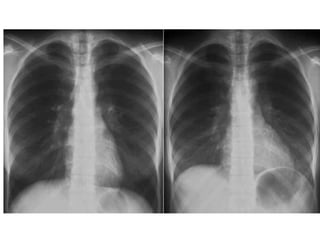

Pulmonary infarction

Chest radiograph with ‘classical’        Chest X ray after 4 days, prior

appearance of a pulmonary infarction –   to treatment, showing massive

a wedge-shaped lesion peripherally set   increase in volume of lesion.

against the pleura